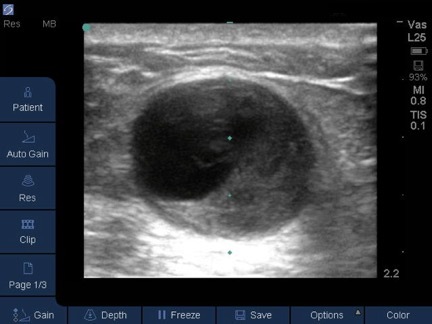

Dialysis Thrombosed Access Image